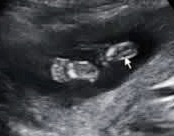

こんばんは。今日で五ヶ月になり診察にいきました。エコー写真を撮って頂いていると始めはうつ伏せになっていましたが3秒間程横向きになった時に、股あたりに白い丸い物が二つ見えました。男の子なのかな?わかる方いらっしゃいませんか?